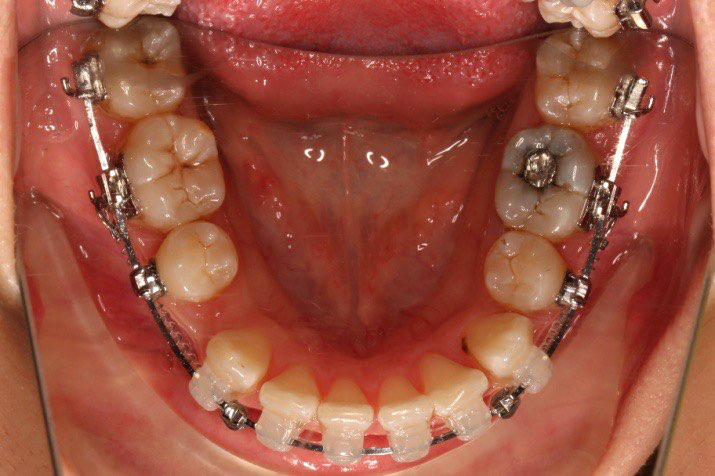

2018.11.14  术后磨牙尖牙I类关系,中线齐,覆合,覆盖正常

牙根基本平行,未见牙根吸收

10 M after Post-Tx

10 M after Post-Tr

2019.08.06  术后  10个月复查